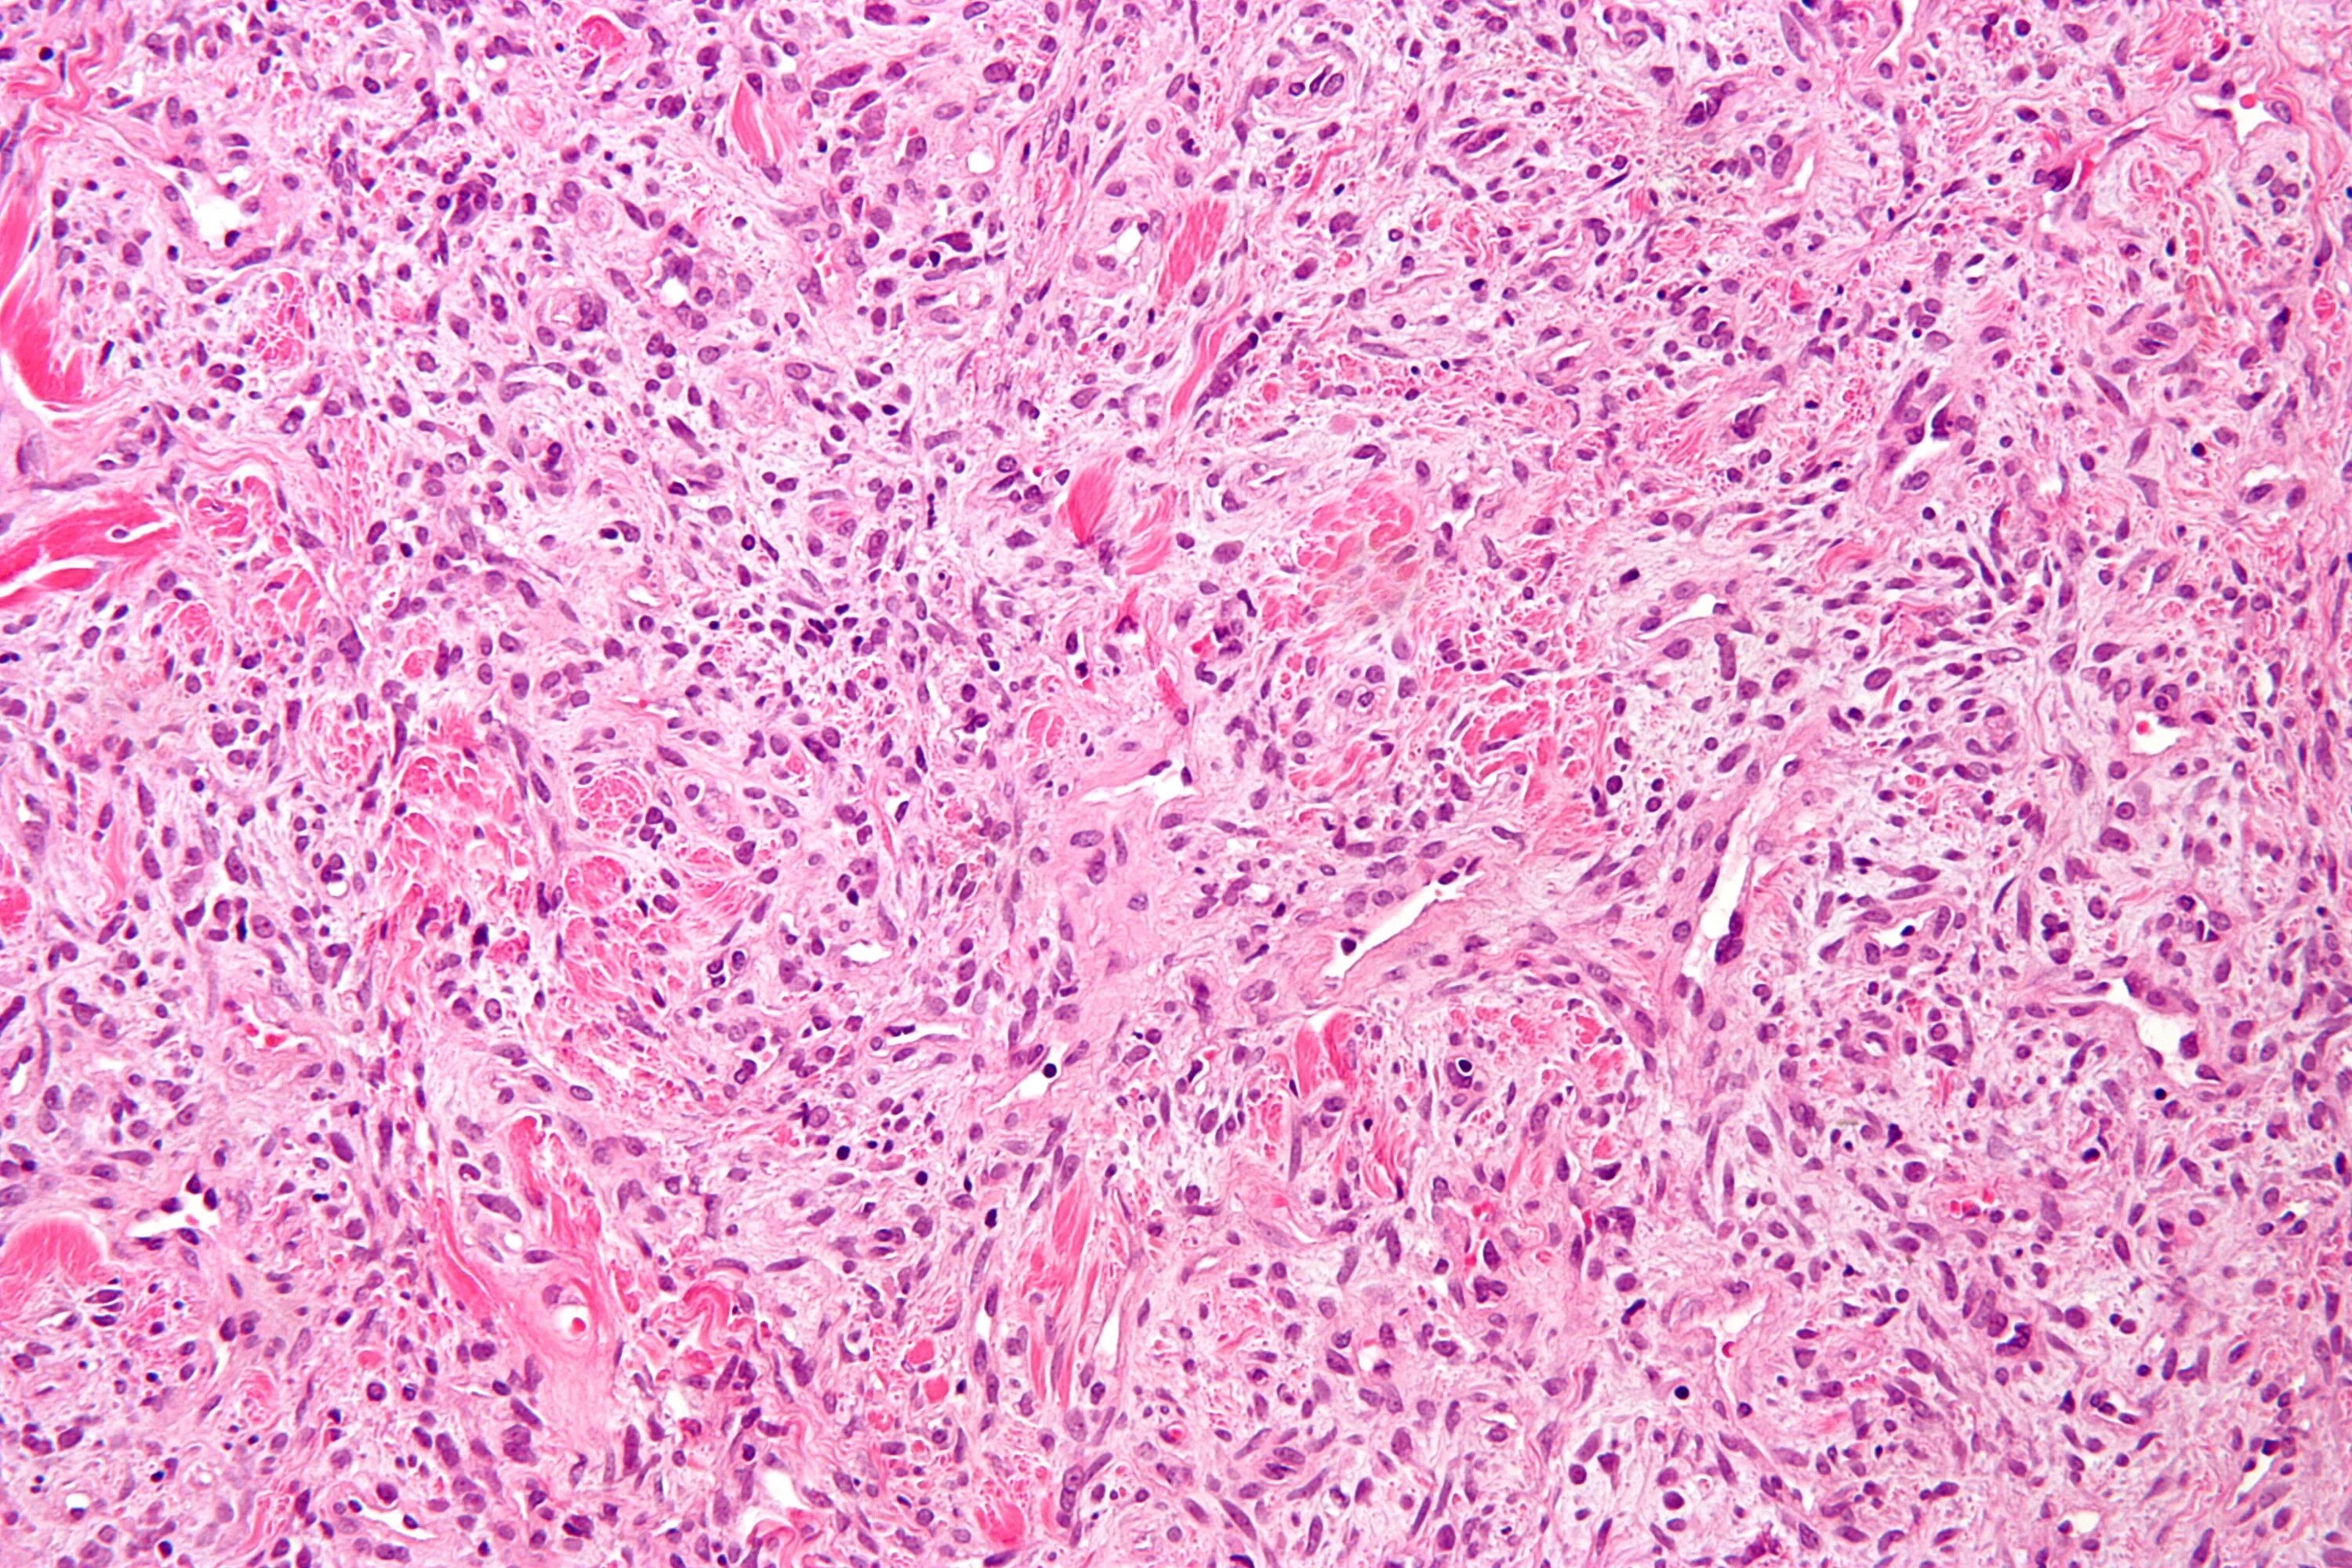

Опухоль с преобладанием стромы на ощупь